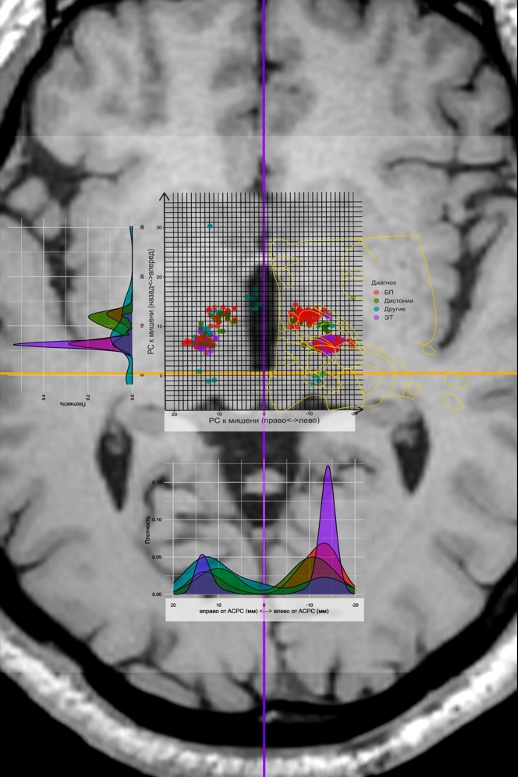

Currently, the precise determination of the impact point is a major challenge. The issue is that the localization of the sonication target is conducted relative to the line connecting the anterior and posterior commissures ( AC–PC), what is the universal coordinate system for patients in functional neurosurgery. At the same time, MRI has its own coordinate system RAS, which is determined by the position relative to the isocenter of the device; additionally, the FUS station has its own coordinate system relative to the focal point. All three coordinate systems relate differently depending on the equipment’s position. To solve this problem, we created a special program in the language R, which allows recalculating coordinates depending on the positions of the zero point of the MRI and FUS station for more accurate target determination and reducing the possibility of error. Figure 5.8 shows an example of the relationship between these coordinate systems, where RAS – these are the coordinates relative to the MRI isocenter, transducer focal – coordinates of the FUS station, and AC–PC target – coordinates relative to the posterior commissure in the plane AC–PC.

Figure 5.9 shows the treatment sonication map for all patients who underwent treatment using the MRgFUS method, on MRI in the axial plane passing through the line AC–PC.